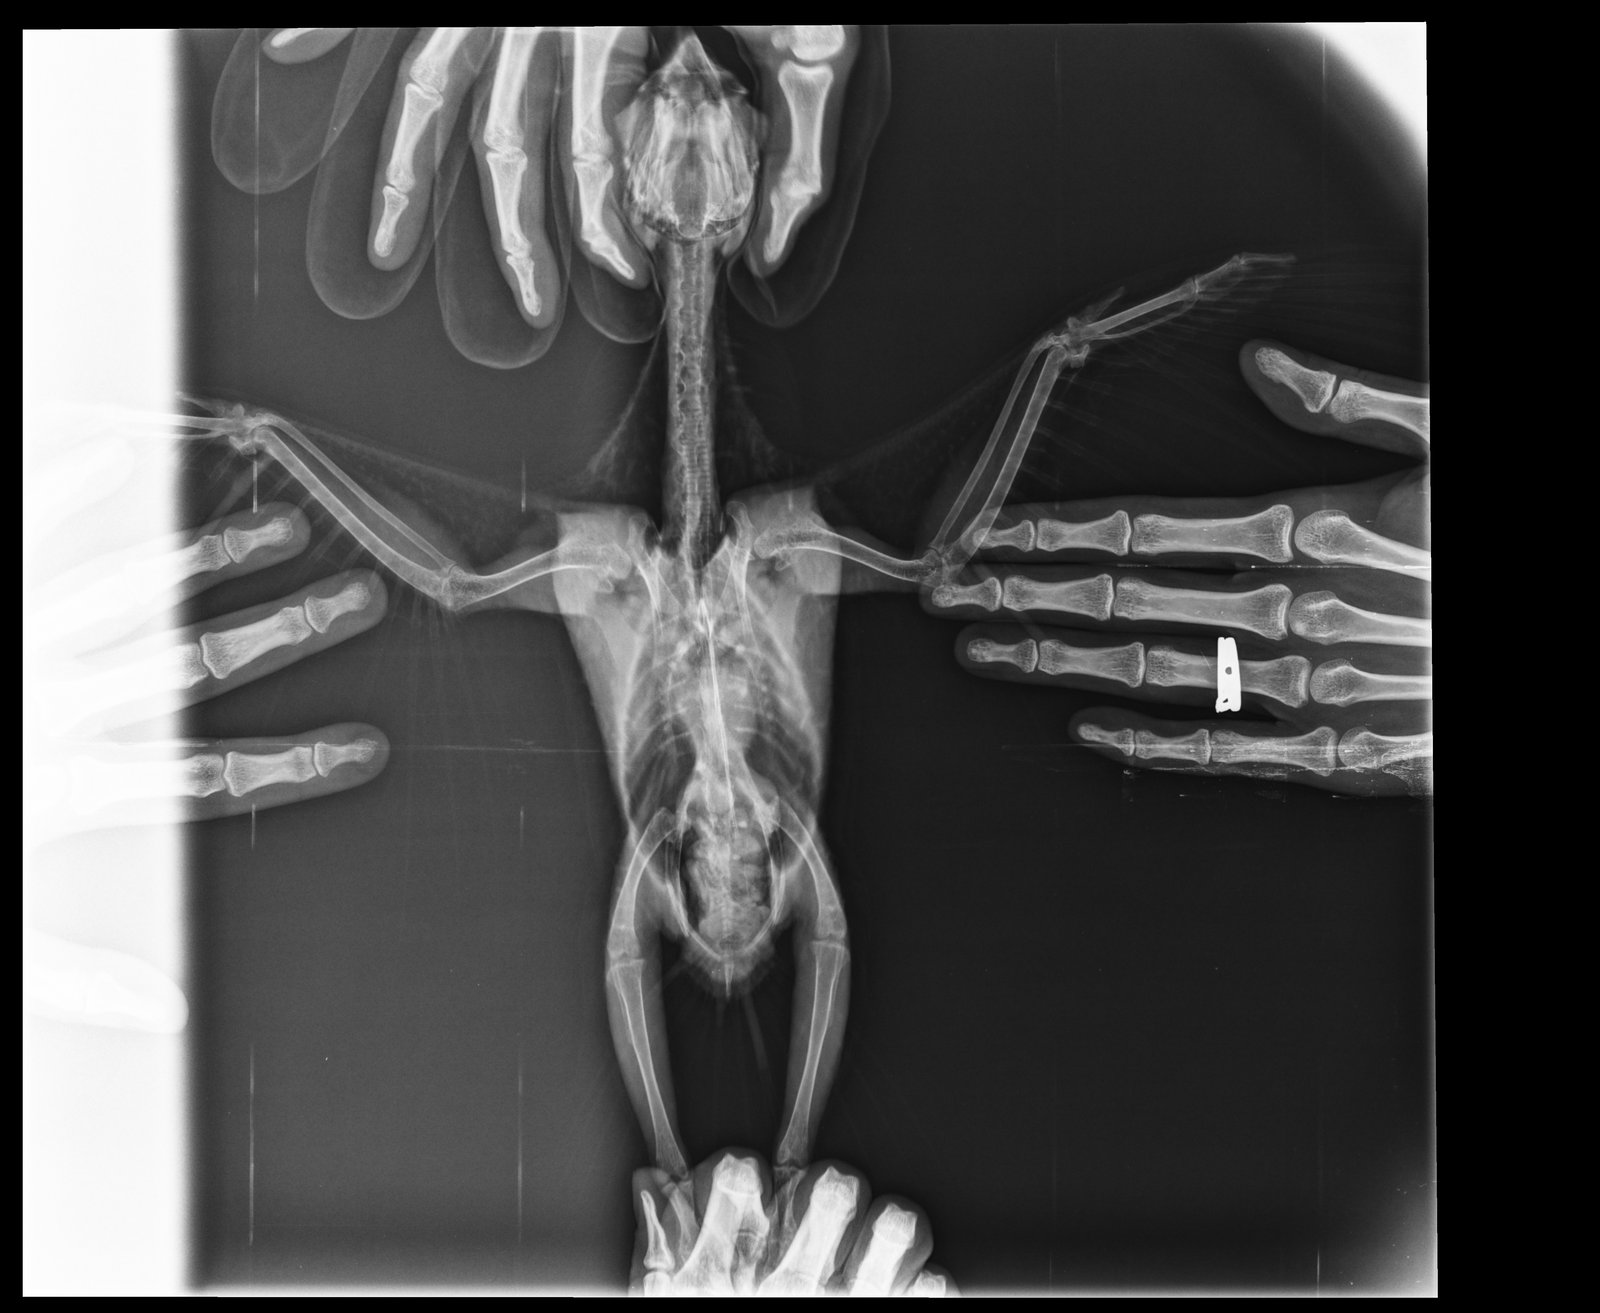

KamaRo Опубликовано 28 ноября, 2018 #8 Опубликовано 28 ноября, 2018 @Nadea про Аронову спросила, т.к. подумала, что она в декрете и сейчас прием не ведет. Аронова стажируется у Волгиной, что говорит о стремлении доктора постоянно расти. А с птицами всегда тяжело, много чего остается за нашим пониманием (не все виды исследований доступны, как у кошек/собак). Если вы у другого врача наблюдались, то о нем тоже хорошие отзывы не помешали, чтобы владельцев птиц направлять к специалисту. При сильном нарушении в работе органов, в т.ч. ЖКТ нужно препараты давать в клюв, с едой мало попадает по назначению. У вас и антибиотики были и довольно тяжелый для печени препарат - орунгал, поэтому лечить уже в комплексе нужно (и гепатопротекторы принимать, и про-пребиотики). Не плохо работают при нарушении микрофолоры - споровит+бифидо-и лактобактерии, фортифлора+бифидо-и лактобактерии, были не плохие результаты на энтероле+пробиотик. Просто какой то метод выбирают и дают в клюв. Споровит (в жидком виде) по 0,3 мл 2 раза в день, методом подбора лакто-и бифидосодержащий пробиотик (мне всегда нравился бифидумбактерин - там 5 доз, на волнушку на глаз флакон делила на 8 приемов, шпажкой откалывала, разводила водой и выпаивала), на амазона наверное 1/2 флакона на 2 приема (утро-вечер). Что касается гепатопроткторов, то их еще с месяц дают после противомикробных препаратов и тоже в клюв. Шрот расторопши в данном случае не особо помогут - это полезная добавка, но в качестве самостоятельного компонента не справится. Гептрал может быть на гепатовет заменить, но он жутко вонючий, но птицы его вполне не плохо переносят, особенно если на 2 приема разделить (но его нужно разводить, т..к суспензия густая и тяжело выпоить). Сейчас вам нужно восстанавливать птицу.